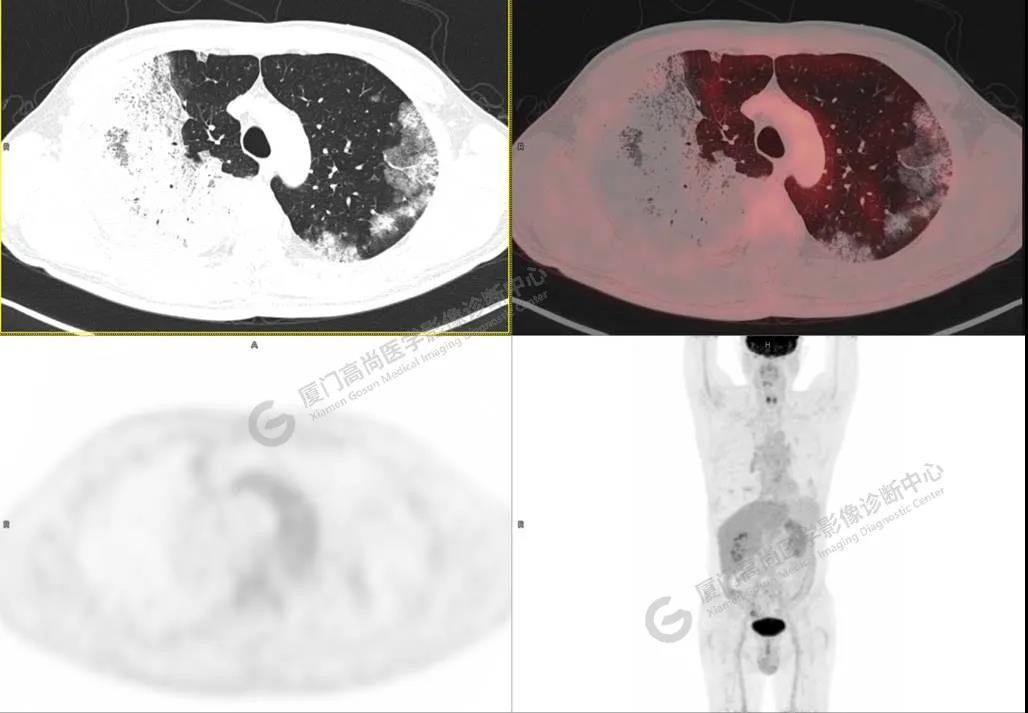

圖1

PET/CT所見:雙肺大片實(shí)變影及磨玻璃影,部分呈地圖樣改變,累及右肺尖,部分放射性攝取輕微增高,SUVmax 1.77,其內(nèi)見多發(fā)支氣管充氣征象。

影像診斷: 雙肺大片實(shí)變影及磨玻璃影,大部分代謝不高,局部代謝輕微增高,考慮肺泡蛋白沉積癥,建議病理學(xué)檢查或肺泡灌洗物檢查。

影像學(xué)表現(xiàn):HRCT上雙肺斑片影,以肺門為中心呈蝶翼狀對稱分布;病變可隨機(jī)分布在中央?yún)^(qū)、周圍區(qū)或全肺葉,病灶與正常分組織分界清楚,呈典型“地圖樣”改變;有支氣管充氣征,但表現(xiàn)為充氣支氣管細(xì)小且數(shù)量及分布稀少;“碎石路”征由彌漫性磨玻璃影及內(nèi)部網(wǎng)格樣小葉間隔增厚組成(鋪路石樣表現(xiàn))。無空洞、蜂窩狀改變、淋巴結(jié)腫大、胸腔積液及明顯實(shí)變等。肺內(nèi)病灶累及范圍、磨玻璃密度高低與PAP患者的病情嚴(yán)重程度相關(guān),嚴(yán)重者病灶累及全肺,同時出現(xiàn)肺內(nèi)大片實(shí)變,并見充氣支氣管征象。PAP影像學(xué)表現(xiàn)程度與臨床癥狀、體征嚴(yán)重程度不成比例,表現(xiàn)為影像改變重,臨床癥狀輕。